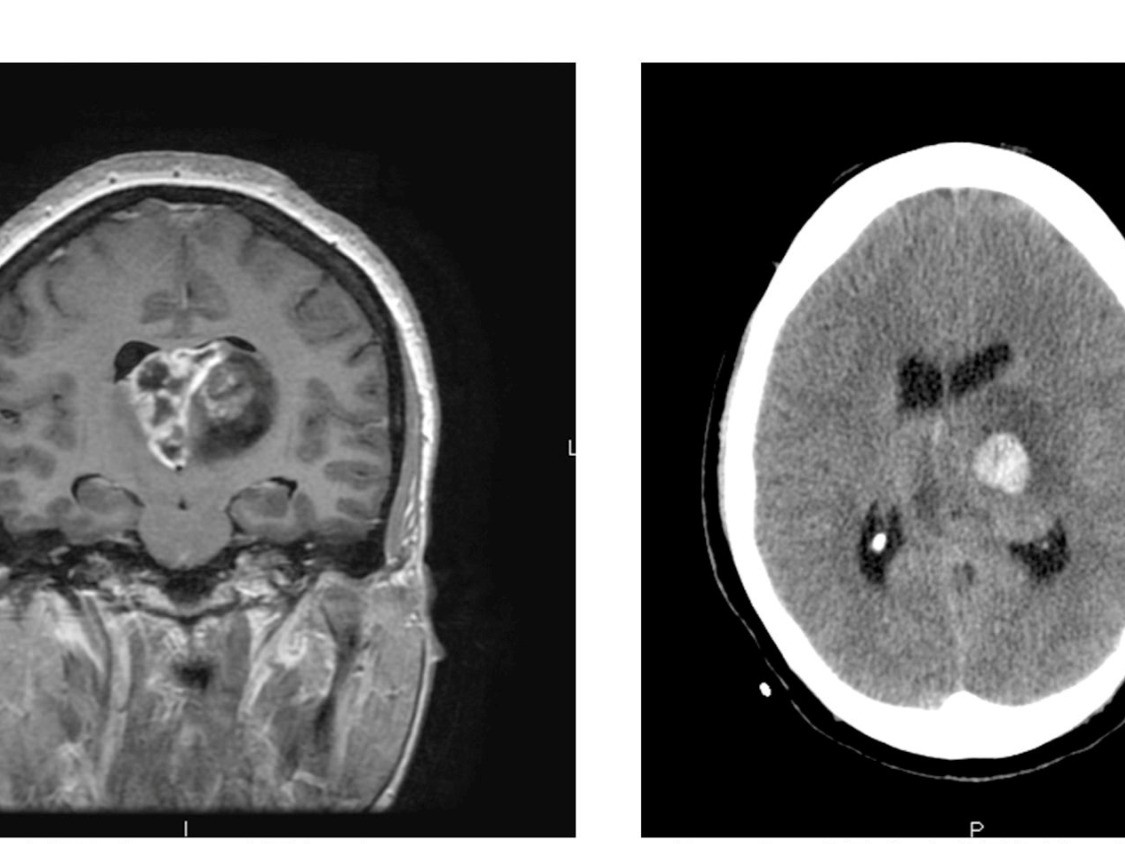

كما بيّن الفريق البحثي أن التقنية الجديدة قد تُطبَّق مستقبلاً على أنواع أخرى من السرطان، خصوصاً تلك التي تتسم بقدرتها على تعطيل الاستجابة المناعية مثل سرطان البنكرياس وسرطان الدماغ.